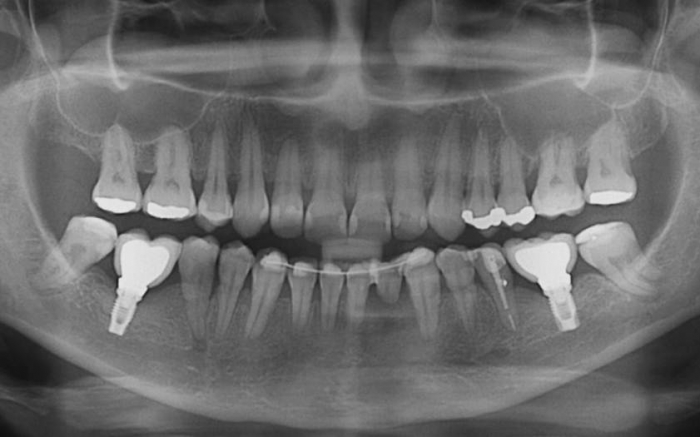

Raio X com próteses fixas em porcelana e encaminhada para extração de incisivo com reabsorção radicular